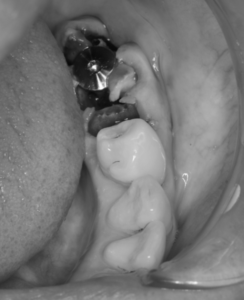

左下を抜いたところに1本目のインプラントが入りました。

抜歯即時埋入の状態、インプラントの方が、抜いた歯よりも径が細いため、周りに隙間が出来てしまいます。その周りの隙間には人工骨を入れて、後々骨になるような工夫を施します。

中の人工骨(顆粒)が漏れてこないように、膜を上に置いて、縫合している状態です。